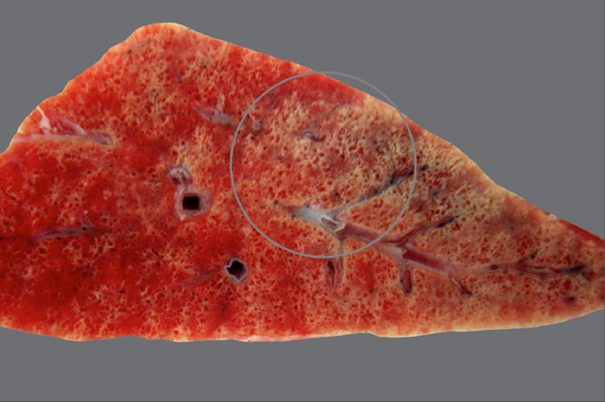

Rind, Niere: Hochgradige chronische diffuse Amyloidose der Niere (Amyloidnephrose)

Beschreibung:

Nierenrinde hellbeige

Oberflächefeingranuliert, speckig

die Renculi erscheinen prominent

derbe Konsistenz

Hintergrundwissen/ Pathogenese/Ätiologie

- Amyloid ist ein fibrilläres Protein, in dem die β-Faltblattstruktur dominiert vermehrter Anfall durch

gesteigerte Synthese oder unvollständige Proteolyse

- Amyloidnephosen v.a. bei Rind, Hund, Katze

AA Amyloid:

- In der Niere meist reaktive systemische Amyloidose: chronischen Entzündungsprozessen ->

gesteigerte Synthese von Serum-Amyloid-A-Protein (Akute-Phase-Protein) durch Hepatozyten ->

Abgabe ins Blut sekundäre Ablagerung von AA-Amyloid vor allem in den Glomeruli

- Familiäre Amyloidose (z.B. Shar-Pei, Abessinerkatze)

AL-Amyloid:

- Selten, z.B. beim Multiplen Myelom

- Beeinträchtigung der glomerulären Filtration durch vermehrte Durchlässigkeit -> Proteinurie, nephrotisches Syndrom

- Differentialdiagnose: Lymphom